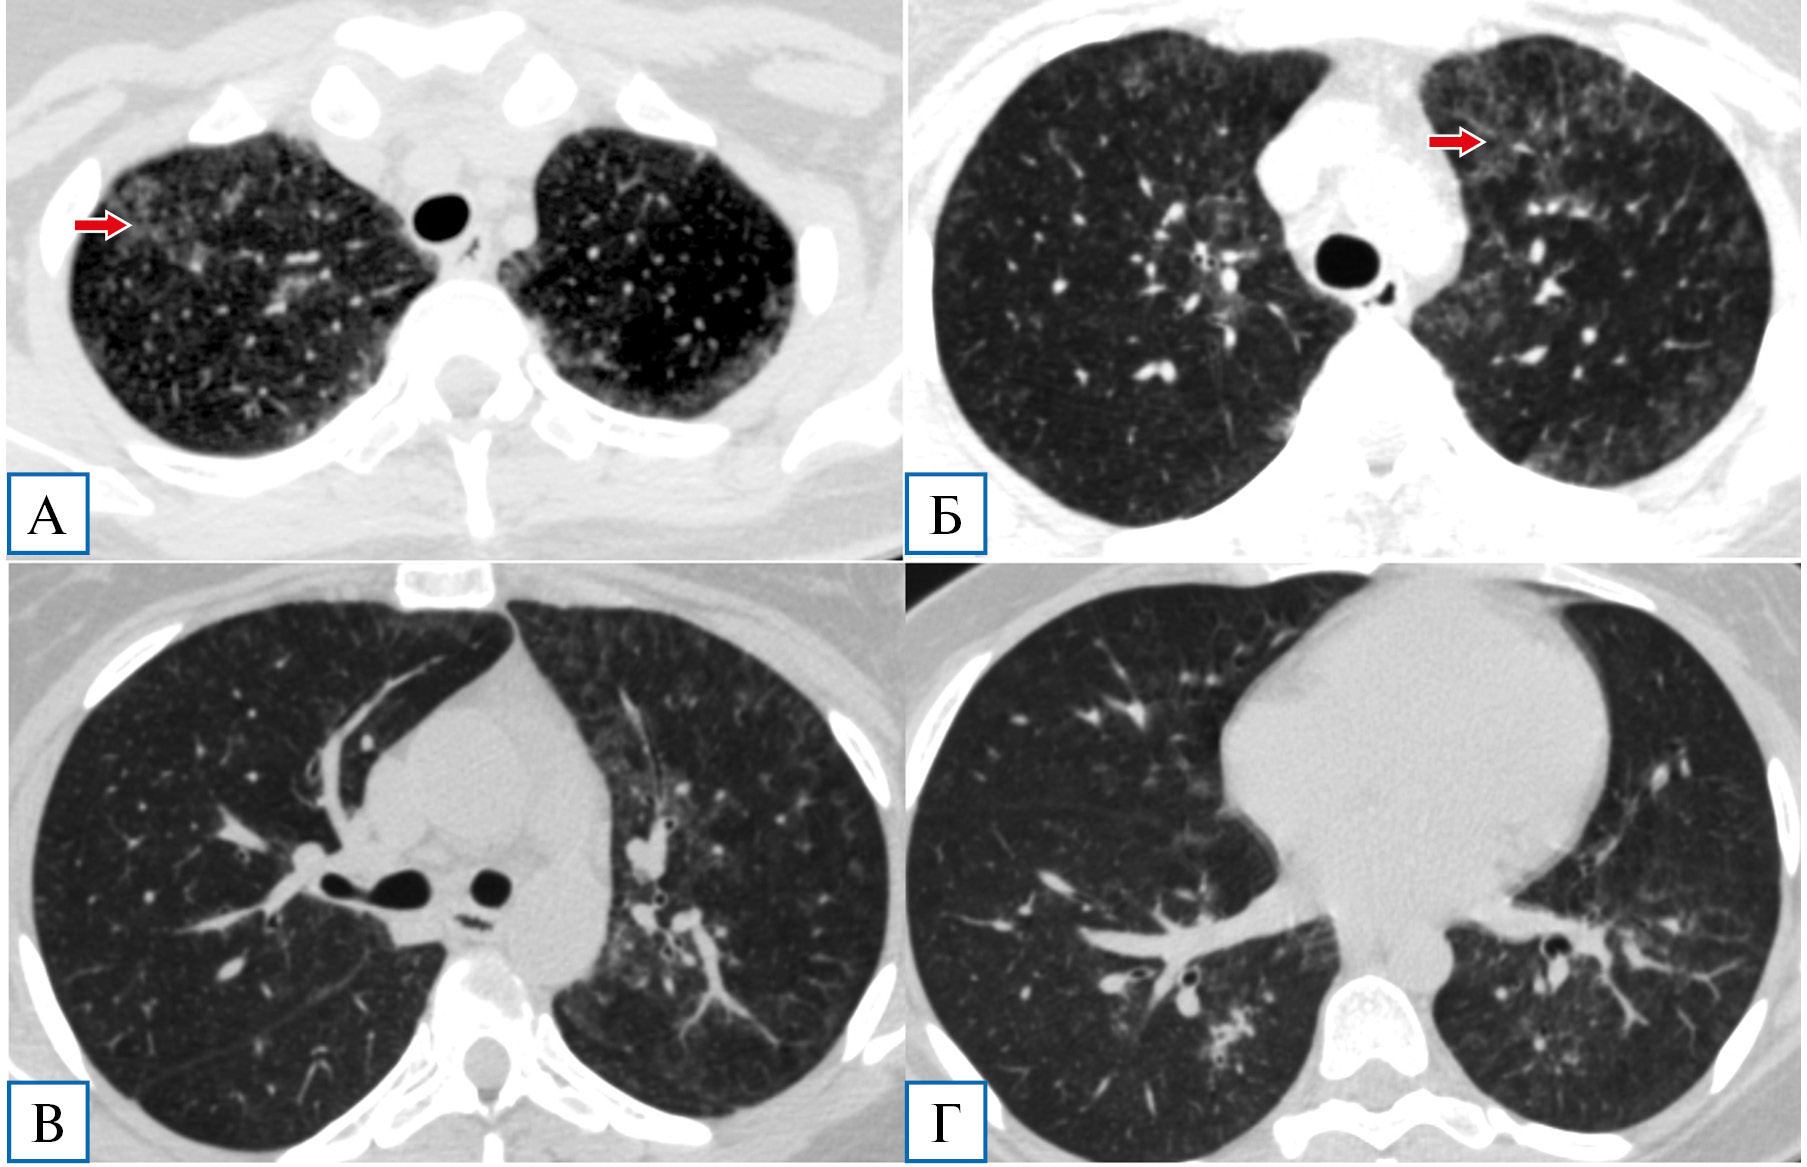

При компьютерной томографии органов грудной полости выявлены распространенные субтотальные зоны «матового стекла», в верхних отделах на фоне наиболее интенсивных зон — «воздушные ловушки»: первоначально КТ-картина расценена как проявления двусторонней вирусной пневмонии (КТ3/4) (рис. 1).

Рис. 1. Пациентка Я., 29 лет: компьютерная томография грудной клетки в день госпитализации

Примечание. Диффузные сливные зоны «матового стекла», почти равномерно распределенные как в верхних (А, Б), так и в нижних отделах легких (В, Г), на фоне которых визуализируются участки повышенной прозрачности — «воздушные ловушки» (показаны стрелками на А и Г).